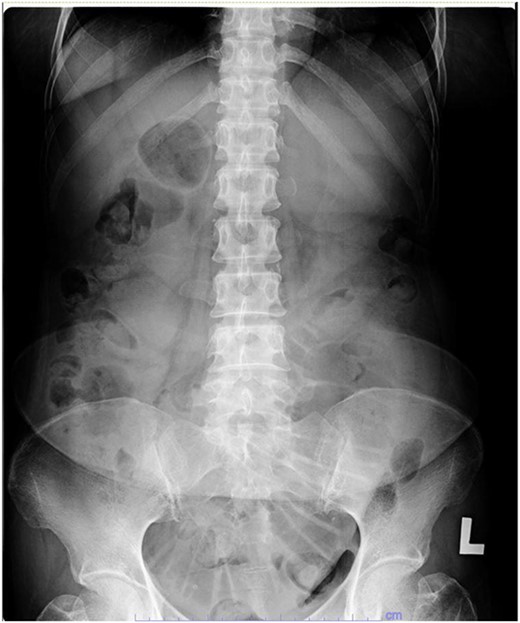

Our patient underwent an urgent midline laparotomy and small bowel resection with primary anastomosis of the small bowel. Small bowel intussusception was seen at 110 cm from the ileocecal valve. The small bowels were grossly dilated proximally from the intussusception (Fig. 4). The primary anastomosis was done with a linear stapler. Multiple lymph nodes were palpable at the surrounding mesentery of the affected small bowel at the point of intussusception. Other parts of the small bowel appeared healthy, and there were no obvious liver nodules or peritoneal nodules seen or felt.

Small bowel noted to be grossly dilated proximal to the site of intussusception.